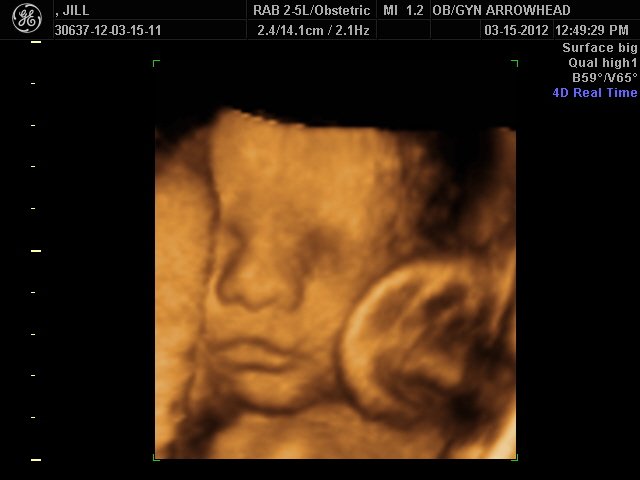

We offer complimentary 3D/4D Ultrasounds to all our OB patients around 30 weeks! The following photos are some examples of our work, shown with permission from our patients.